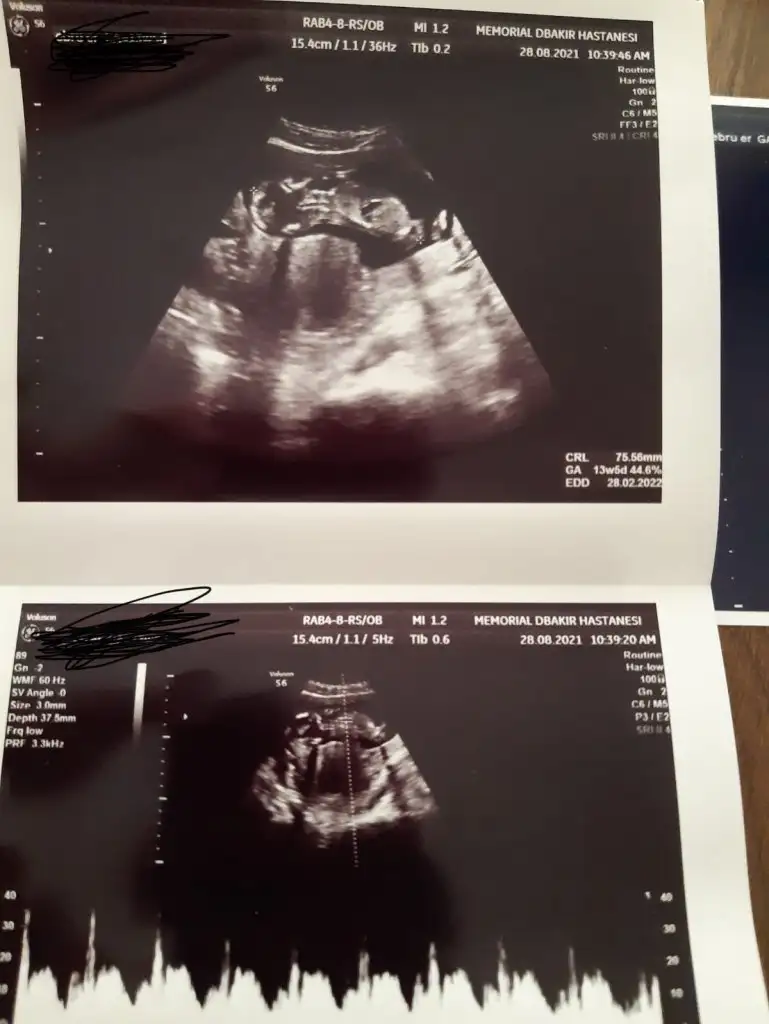

Bizde bugün kontrolden çıktık 12+3 haftalığız ,doktor cinsiyet için emin olamadı resimlerden siz yorum yapabilirmisiniz Ikra meyra

• D5327C6B-FBE3-4BB2-AAFD-29FD27EC4F4A.webp

36,1 KB · Görüntüleme: 115

• 4E3EF953-E6C9-4F89-91E6-5BF3ECF5CB0E.webp

38,4 KB · Görüntüleme: 108